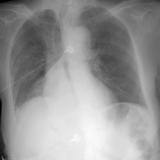

RLL Collapse 1 PA

Date: 02/28/2004

Views: 3442